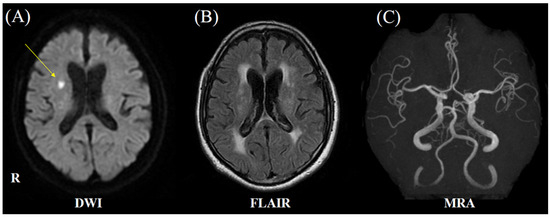

2. Case Presentation